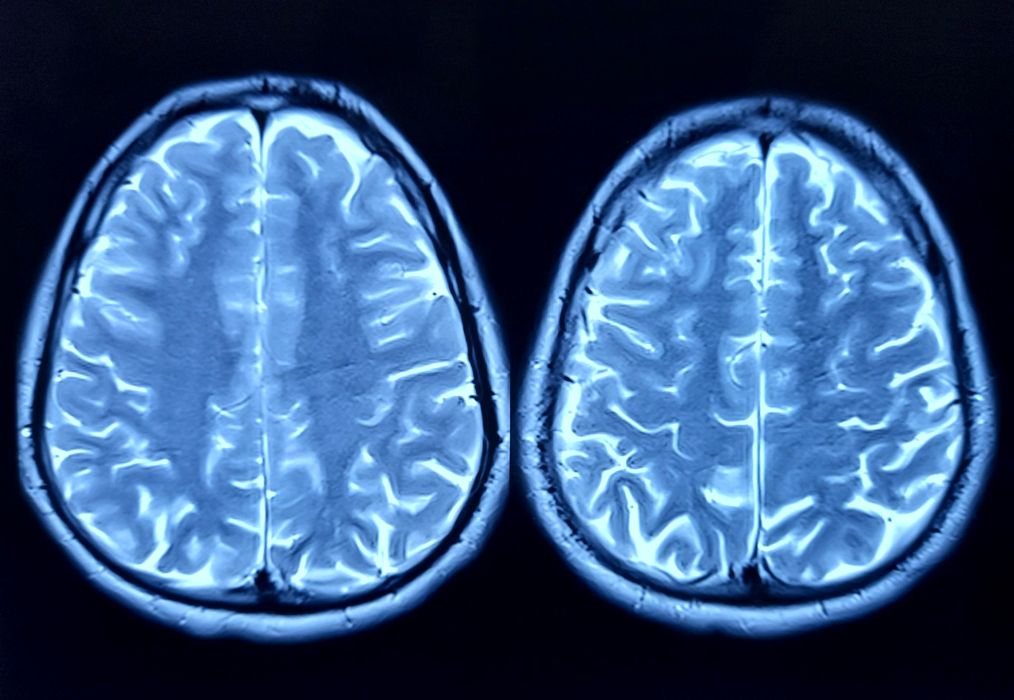

Ce s-a întâmplat după ce o femeie a auzit voci care îi spuneau că are o tumoare pe creier?

În 1984, o femeie perfect sănătoasă a început, brusc, să audă voci care îi spuneau că are o tumoare pe creier. Experiența a speriat-o profund, făcând-o să se teamă pentru sănătatea ei mintală, așa că […]